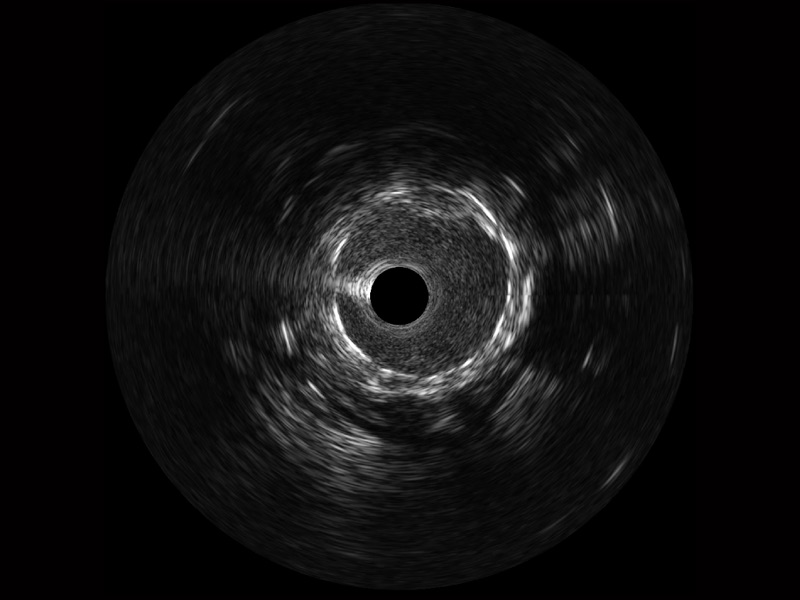

宽频成像,兼具高分辨力和更大穿透深度

太阳成tyc7111cc官网超宽频成像技术覆盖20-80MHz1或20-90MHz2频率范围, 提供优异的分辨力同时也保证充足的穿透深度

1.SonoSound? Crystal导管对比传统IVUS导管成像,太阳成tyc7111cc官网宽频IVUS图像的近场支架梁显影更细腻,远场中膜外血管仍清晰可辨,兼顾远中近,兼顾分辨力与穿透深度